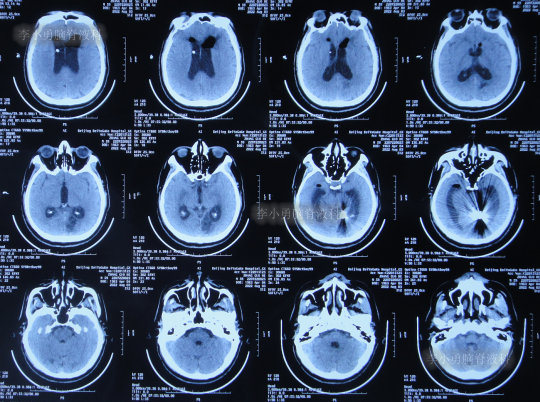

在当地的某医院进行康复治疗1个月的时间,患者症状无改善,期间3次查头颅CT(图-10、图-11、图-12)均示仍脑积水。

图-10:2022年6月20日头颅CT

图-11:2022年7月1日头颅CT

图-12:2022年7月12日头颅CT

因患者症状一直没有改善,家属经过打听后于2022年7月22日来到北京北亚骨科医院的李小勇脑脊液科。

2022年7月22日(脑动脉瘤栓塞术后126天,即脑室腹腔分流术40余天仍脑积水)住入李小勇脑脊液科;入院时:意识欠清,时有言语错乱,情感淡漠,小便失禁,坐着自己起不来,搀扶下能站立,但迈不开步,腹部有手术疤痕(图-13)。

入院时查头颅CT示脑室分流术后仍脑积水(图-14)。

图-14:2022年7月22日头颅CT